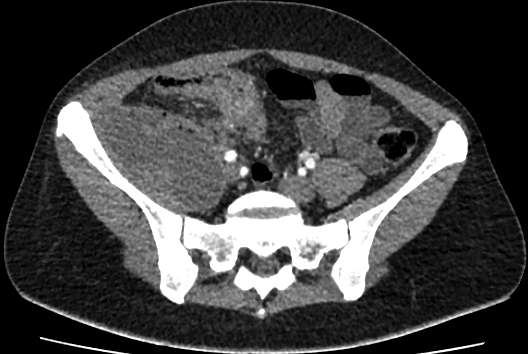

КТ-исследование абсцесса малого таза: Визуализация и диагностика

Раздел: Фотоальбом решений